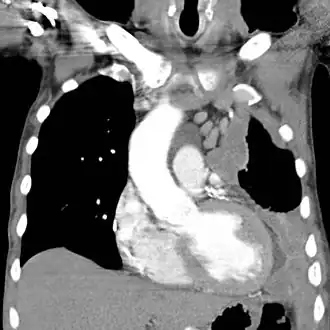

Компьютерная томограмма показывающая левостороннюю мезотелиому с увеличенным медиастинальным лимфатическим узлом | |